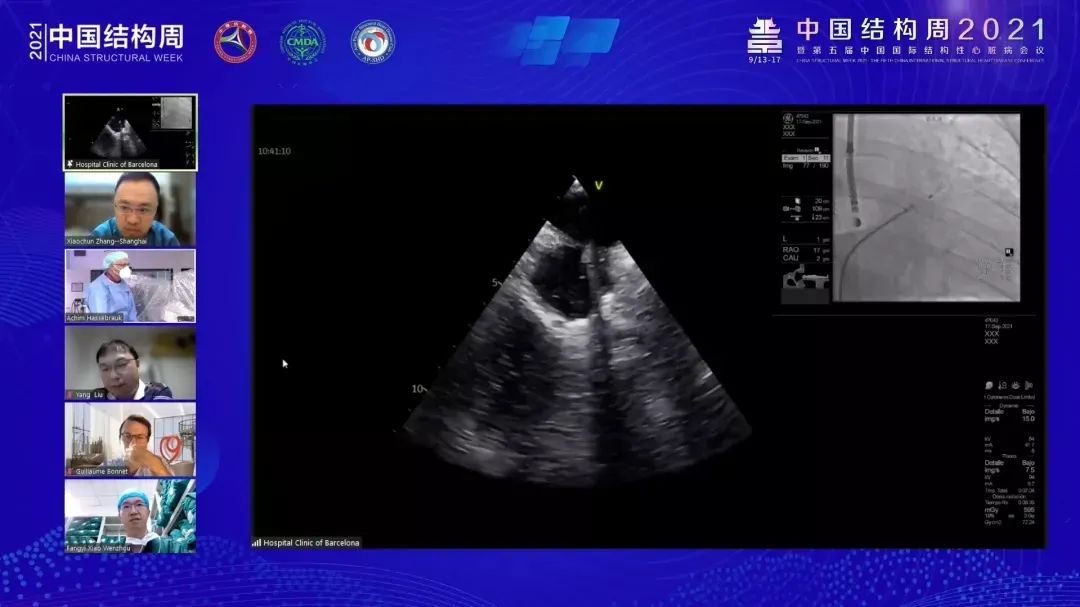

ICE指引下的左心耳封堵手术,无需麻醉与TEE,大大优化了手术步骤,为患者减少了痛苦,储慧民教授结合多年来的临床工作经验,分享了ICE在LAAC中的运用经验,详细论述了“LOVE”工作流程,并强调了ICE在LAAC中的优势。储慧民教授认为,我们可将心脏模型构建为一个正方体,左心耳就恰好位于该正方体的左前上角,术者沿X、Y、Z轴分别进行扫描,即可全方位、无遗漏地观察到左心耳的完整形态;随后Saibal Kar教授为我们带来了一例经典的LAAC直播病例。该病例全程在TEE指导下完成,术前评估了左心耳形态及有无血栓的发生。Saibal Kar教授表示,与ICE相比,TEE的优势体现于可以在多个平面上进行检查。

TEE下精彩手术片段